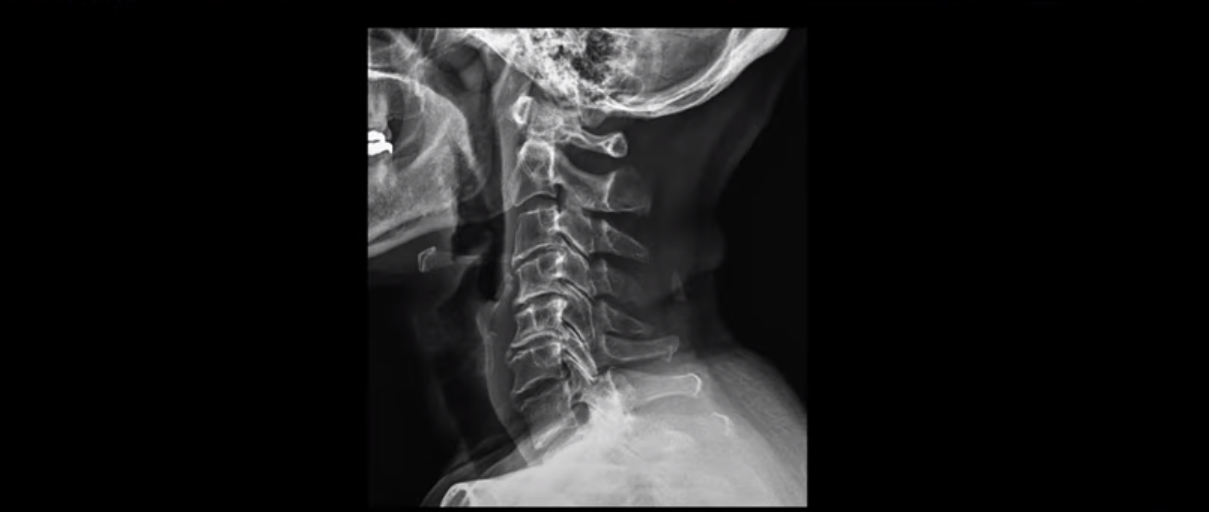

이 환자분 X-ray, MRI 보고 간단히 설명 드린 후 왜 목디스크 치료가 허리디스크에 비해 훨씬 더 쉬운지 자세히 설명 드리겠습니다.

X-ray 보시다시피 완전 일자목 거북목에다 여러 마디가 전부 다 퇴행이 심하며

뼈 모양의 변형도 매우 심합니다.

X-ray로 봐도 신경 구멍들이 좁아진 게 보입니다.

이런 걸 협착이라고 부르는 거죠. 이 분의 가장 불편한 증상은 20년간 아픈 만성적인 목통증과 어깨통증, 두통과 눈 통증인데 최근 들어 가증 불편한 증상은 목이 아예 돌아가지 않는 겁니다. 그래서 운전할 때도 사이드 미러를 보려면 몸을 돌리셨다고 하는데요. 주사 효과도 전혀 없고 대학병원에서도 디스크와 협착인데 그냥 약먹고 운동만 하라고 하면 이 환자는 어떻게 해야 할까요?

이 환자분도 아까 X-ray에서 보여드렸듯이 아주 심한 일자목, 거북목이 있고 그 결과로 목의 거의 모든 마디가 다 퇴행이 진행되어 있죠. 즉 거북목은 모든 목질환, 특히 목디스크, 목협착증의 어머니 질환이며 그래서 목디스크를 치료하기 위해서는 반드시 거북목 때문에 짧아지고 뭉치고 굳고 뒤틀린 목 주변 근육들을 잘 치료해줘야 합니다.